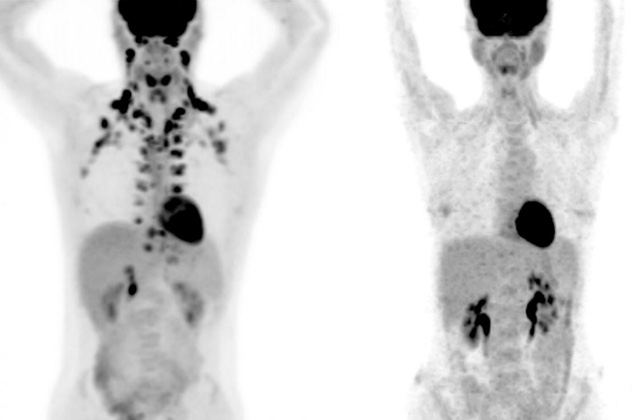

Ảnh PET của người có nhiều mỡ nâu ở cổ và xương sống (trái), trong khi người còn lại không có mỡ nâu.

Trong khi mỡ trắng tích trữ calo và chiếm khoảng 90% tế bào chất béo của cơ thể, mỡ nâu là yếu tố tiêu hao năng lượng, đốt cháy mỡ thừa và sinh nhiệt. Tuy nhiên, lợi ích sức khỏe của mỡ nâu ít được nghiên cứu bởi nó khó tìm, thường nằm sâu trong cơ thể, thậm chí bị nhầm lẫn với các khối u.Trong nghiên cứu đăng trên tạp chí Nature Medicine, các chuyên gia tại Bệnh viện Đại học Rockefeller (Mỹ) cho biết nhờ kiểm tra 130.000 kết quả chụp ảnh (PET) của hơn 52.000 bệnh nhân, họ có thể nhìn thấy mỡ nâu và phát hiện thêm tác dụng của loại mỡ này. Theo đó, gần 10% trong số các bệnh nhân có mô mỡ nâu và họ ít gặp vấn đề về sức khỏe hơn. Cụ thể, chỉ có 4,6% bệnh nhân có mỡ nâu mắc bệnh tiểu đường tuýp 2, trong khi tỷ lệ này nhóm người không có mỡ nâu là 9,5%. Tương tự, chỉ 18,9% số người có mô mỡ nâu có mức cholesterol bất thường, so với 22,2% số người không có mỡ nâu. Người có mô mỡ nâu cũng có nguy cơ mắc bệnh cao huyết áp, suy tim và bệnh mạch vành thấp hơn. Các kết quả thậm chí còn chỉ ra rằng mỡ nâu giúp đẩy lùi một số tác động bất lợi sức khỏe ở những người bị béo phì.

"Lần đầu tiên, mỡ nâu được phát hiện có liên quan đến việc giảm nguy cơ mắc một số bệnh. Những phát hiện này khiến chúng tôi tin tưởng hơn về tiềm năng sử dụng mỡ nâu trong điều trị bệnh" - Paul Cohen, bác sĩ cấp cao tại Rockefeller, cho biết. Theo ông, nhiệm vụ tiếp theo của giới nghiên cứu là trả lời câu hỏi "làm thế nào chúng ta có thể tăng lượng mỡ nâu trong cơ thể?".Mỡ nâu chủ yếu nằm ở bên cạnh cổ, đôi khi sẽ chạy xuống vai và cánh tay hoặc được dự trữ tại khu vực ngay phía trên xương đòn (xương quai xanh). Các vị trí lưu trữ mỡ nâu phổ biến khác bao gồm phần lưng trên, giữa 2 bả vai, và dọc theo 2 bên cột sống. Lượng mỡ nâu nhiều nhất trong cơ thể chỉ lên tới vài ounce (1 ounce = 28g), hơn nữa, lại nằm sâu dưới da, nên mỡ nâu sẽ không dễ nhìn thấy từ bên ngoài như mỡ trắng.